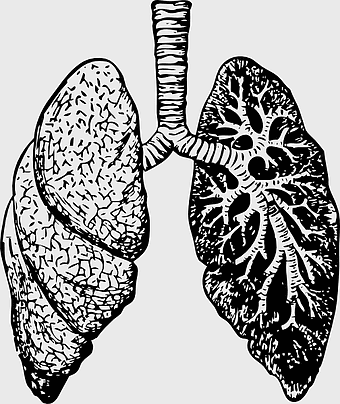

human lung anatomy, respiratory system illustration, heart and lungs diagram, bronchus structure, pulmonary function, thoracic cavity, medical imaging analysis -

lung illustration, cartoon lung, organ diagram, animated lung, respiratory system, human anatomy, medical illustration -

lungs illustration, respiratory system diagram, human lungs anatomy, pulmonary alveolus structure, bronchial tree visualization, trachea and bronchi, lung lobes detail -

human lungs icon, monochrome lung illustration, breathing organ diagram, anatomy line art, pulmonary tree structure, respiratory system graphic, black and white organ depiction -

lung organ, small lungs, respiratory system, pink trachea, human anatomy, medical illustration, pulmonary health -

lung anatomy sketch, human respiratory system drawing, black and white lung illustration, monochrome human lungs, pulmonary organ diagram, breathing system art, medical illustration of lungs -

Respiratory system anatomy, human breathing process, pulmonary alveoli structure, respiratory therapist training, respiratory health education, lung function diagram, respiratory disease prevention -

human lungs illustration, respiratory system anatomy, carina of trachea, blood vessel in lungs, pulmonary function, respiratory tract diagram, bronchial tree structure -

Lung Respiratory system, trachea and bronchus, pink lungs illustration, breathing anatomy, pulmonary health, respiratory function, medical education visuals